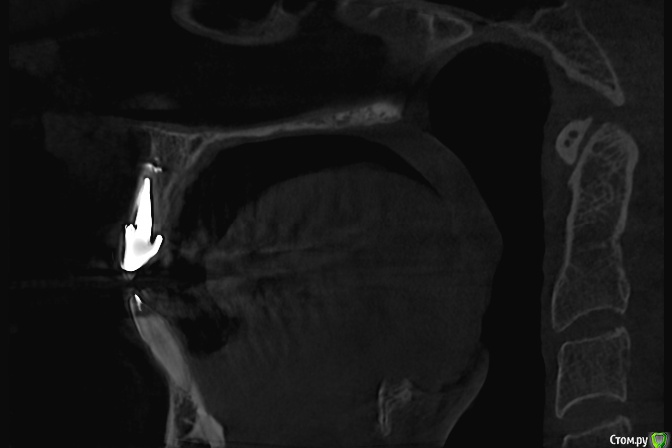

Zelenoglazka Опубликовано 13 мая, 2017 Автор Поделиться Опубликовано 13 мая, 2017 Здравствуйте! В общем продолжение следует...Терапевт, у которого лечила соседний с коронкой зуб, проконсультировался по КТ с их хирургом, оба решили, что кончик канала не запломбирован и требуется резекция с запечатыванием среза специальным цементом (практически дословно цитирую). Я спросила у терапевта про ретроградное пломбирование (хотя сама до конца не понимаю в чем оно заключается), что нет смысла, туда не подлезешь и вообще он не видели, чтобы так делали...Я решила сходить в другую клинику - там хирург, посмотрев внимательно КТ и рентген, сказал, что видит след пломбировоного материала в канале и что резекция мне не нужна и даже может быть опасна расколом корня. А затем увидел на КТ и показал мне признаки возможной трещины корня - вышедший сквозь стенку корня цемент, на которую устанавливается вкладка Ссылка на комментарий

Zelenoglazka Опубликовано 13 мая, 2017 Автор Поделиться Опубликовано 13 мая, 2017 Постаралась найти и сохранить срезы, которые он мне показывал Ссылка на комментарий